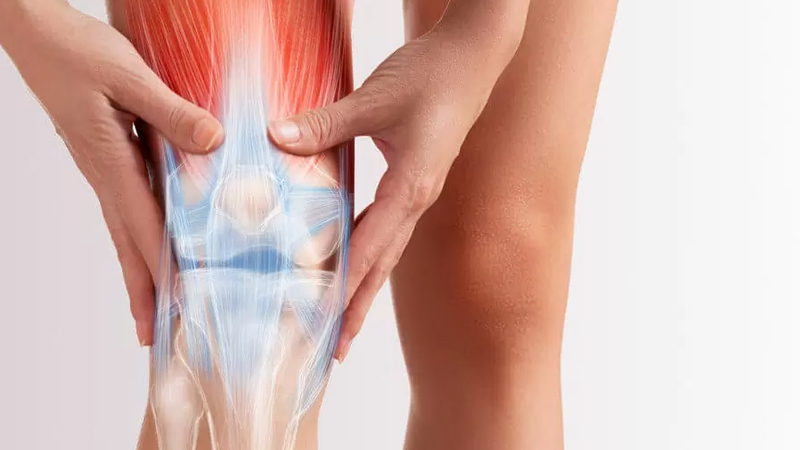

آرتروز زانو یک بیماری مزمن و التهابی است که منجر به تخریب و آسیب در سطح مفصل زانو میشود. در این بیماری، درجه فرسایش و سایش سطح غضروف زانو افزایش مییابد و باعث درد، سفتی و محدودیت حرکت در مفصل میشود. درمان آرتروز زانو معمولاً به مدیریت علائم، کاهش التهاب و افزایش عملکرد مفصل متمرکز میشود. در ادامه، تمرینات و راهکارهایی که ممکن است در مدیریت و کاهش علائم آرتروز زانو مفید باشند را بررسی خواهیم کرد: